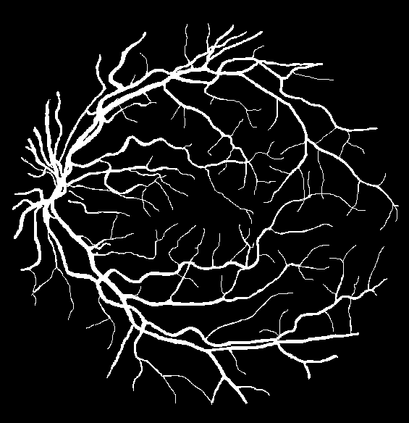

Blood vessel segmentation is crucial for many diagnostic and research applications. In recent years, CNN-based models have leaded to breakthroughs in the task of segmentation, however, such methods usually lose high-frequency information like object boundaries and subtle structures, which are vital to vessel segmentation. To tackle this issue, we propose Boundary Enhancement and Feature Denoising (BEFD) module to facilitate the network ability of extracting boundary information in semantic segmentation, which can be integrated into arbitrary encoder-decoder architecture in an end-to-end way. By introducing Sobel edge detector, the network is able to acquire additional edge prior, thus enhancing boundary in an unsupervised manner for medical image segmentation. In addition, we also utilize a denoising block to reduce the noise hidden in the low-level features. Experimental results on retinal vessel dataset and angiocarpy dataset demonstrate the superior performance of the new BEFD module.